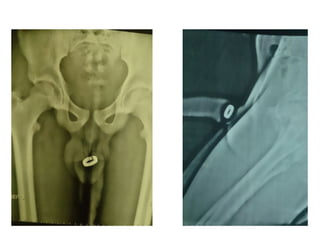

Imagem de corte axial com

janela para tecido ósseo